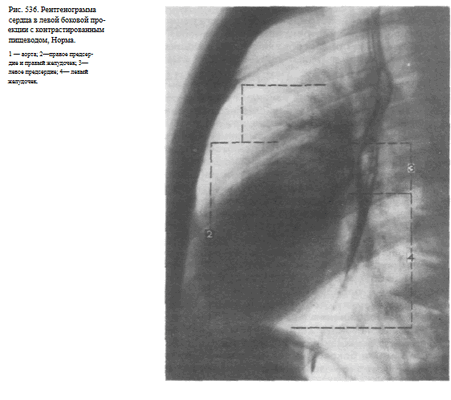

Информативность снимка. По переднему контуру сердца определяются две дуги: верхняя (располагается против тела грудины) образована восходящей аортой, нижняя — передней стенкой правого желудочка. По заднему контуру сердца выделяются также две дуги: верхняя образована левым предсердием (прилегает к передней стенке пищевода) и нижняя образована задней стенкой левого желудочка (рис. 536).

В левой боковой проекции передний контур сердечно-сосудистой тени представлен двумя дугами. Верхняя выпуклая дуга образована восходящей аортой, которая переходит в дугу и нисходящую аорту. Нижняя дуга обусловлена правым желудочком, верхняя часть которого представлена легочным конусом. Правый желудочек прилегает к грудине на протяжении 5-6 см. На границе легочного конуса и восходящей аорты образуется угол открытый кпереди. Между грудиной и передним контуром сердечно-сосудистой тени прослеживается треугольной формы участок, образованный проекцией легких.

По заднему контуру сердечно-сосудистой тени сверху вниз прослеживается аорта, легочной ствол и частично сосуды корней легких. Нижняя дуга образована левым предсердием и левым желудочком. Левый желудочек прилегает к диафрагме на протяжении 5-6 см, как и правый желудочек к грудине.

Рентгенограмма органов грудной клетки в боковой проекции. Обозначения:.

В левой боковой проекции прослеживаются все отделы аорты. Величина ретрокардиального пространства 2-4 см. Пищевод прилегает к левому предсердию и имеет вертикальное направление.